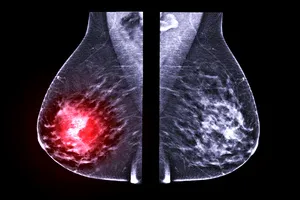

유방암 병기별 특징 및 예후

유방암의 병기는 암의 진행 정도를 나타내는 지표로, 종양의 크기(T), 림프절 전이(N), 원격 전이(M) 등을 종합적으로 고려하여 분류합니다. 병기별 특징과 예후는 다음과 같습니다.

| 병기 | 종양(T) | 림프절(N) | 원격 전이(M) | 예후 |

| 0기 | 상피내암 | 없음 | 없음 | 매우 좋음 |

| 1기 | 2cm 이하 | 없음 | 없음 | 매우 좋음 |

| 2기 | 2-5cm 또는 2cm 이하이지만 림프절 전이 | 1-3개 전이 | 없음 | 좋음 |

| 3기 | 5cm 초과 또는 흉벽 침윤, 또는 림프절 광범위 전이 | 4개 이상 전이 또는 쇄골상 림프절 전이 | 없음 | 보통 |

| 4기 | 모든 크기 | 모든 림프절 | 다른 장기로 전이 | 나쁨 |